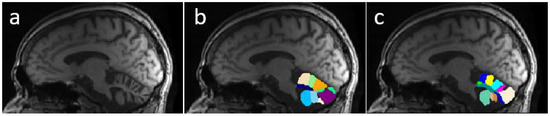

Despite the excellence of the existing methods and the reported results, none of this research is oriented to correctly segment and determine all important fissures in cerebellum of patients with neurodegenerative diseases. Figure 1 shows a comparison between segmentations produced by CERES and ACAPULCO for one magnetic resonance from a SCA2 patient with severe cerebellar atrophy. It can be seen that CERES made a better recognition of increased fissures than ACAPULCO, however, some of them have been incorrectly classified as cerebellar tissue. This phenomenon must be related to the training images and labels for both methods, but it should have great impact on the calculation of volumes for the affected parts. As the fissures are classified as cerebellar tissue, the resulting volumes should be larger than the actual ones, giving an incorrect idea of the atrophy produced in the patient’s cerebellum. Images were generated with ITK-Snap software [21], CERES segmentation was obtained through the web portal (https://www.volbrain.upv.es/, accessed on 5 December 2021), and ACAPULCO segmentation was obtained by using a docker container shared by the authors in the original paper [1].

As can be seen, our model M2 achieved higher DSC than both methods. Mean DSC were 0.973, 0.903 and 0.924 for M2, Acapulco and CERES, respectively. CERES performed better than ACAPULCO in the segmentation, but in general both methods only identify the largest fissures, and a substantial part of the small fissures is misclassified. We think that this event is related with the segmentations used in both methods as a training/knowledge base, since both methods were used without any modification. The best behavior for both methods was on segmenting the first resonance image, corresponding to a healthy control.

Figure 5 presents an example of segmentation produced by the three models for a subject in our dataset. As the figure shows, ACAPULCO (Figure 5d) only detected parts of the biggest fissures, while the smaller ones are classified as cerebellar tissue. CERES (Figure 5c) recognized fissures better than ACAPULCO, but some of them are also misclassified. Furthermore, some irregularities are present in the front of the cerebellum, leaving some holes in the mask produced by CERES. Segmentations obtained by model M2 (Figure 5b) are very close to the real ones, correctly recognizing most of the fissures.

Table 8 shows a comparison for the OC scores achieved by the three methods. Mean scores for M2, ACAPULCO and CERES were 0.987, 0.994 and 0.988, respectively. Results are very close between approaches, but in general terms, ACAPULCO achieved higher OC scores. This is a logical conclusion, as ACAPULCO tends to misclassify fissures. As a result, the original masks are almost entirely contained in segmentations produced by ACAPULCO. The same happens with segmentations produced by CERES.

In Table 9 are included the results of the SP analysis for the three models. It can be appreciated that M2 model achieved the higher scores, followed by CERES, and finally ACAPULCO. The mean values are 0.994, 0.971 and 0.964, respectively.

Table 7, Table 8 and Table 9 clearly indicate that model M2 produced better segmentations than ACAPULCO and CERES. Higher DSC and SP combined with lower OC, means that our approach correctly identifies the most of fissures on the cerebellum.

Figure 1. Comparison between segmentations on MRI of SCA2 patient. In (a) the original imaging, in (b) segmentation produced by ACAPULCO, and in (c) segmentation obtained by CERES.

Figure 5. Example of segmentations produced by the approaches for a sample image from our dataset. Original mask (a), followed by segmentation produced by M2 (b), CERES (c) and ACAPULCO (d).